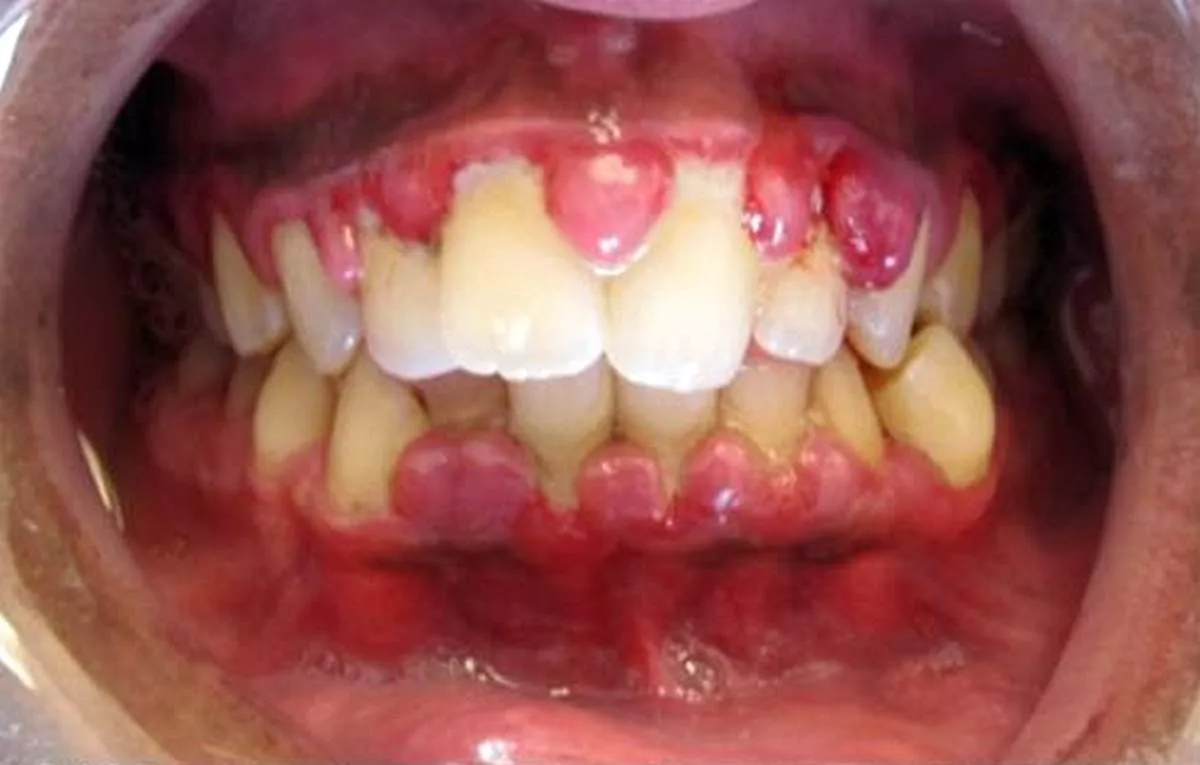

Ingyulladás képe

Súlyos gingivitis hiperpláziával (szerző: Lesion, liszensz: CC BY-SA 3.0, Wikimedia Commons)